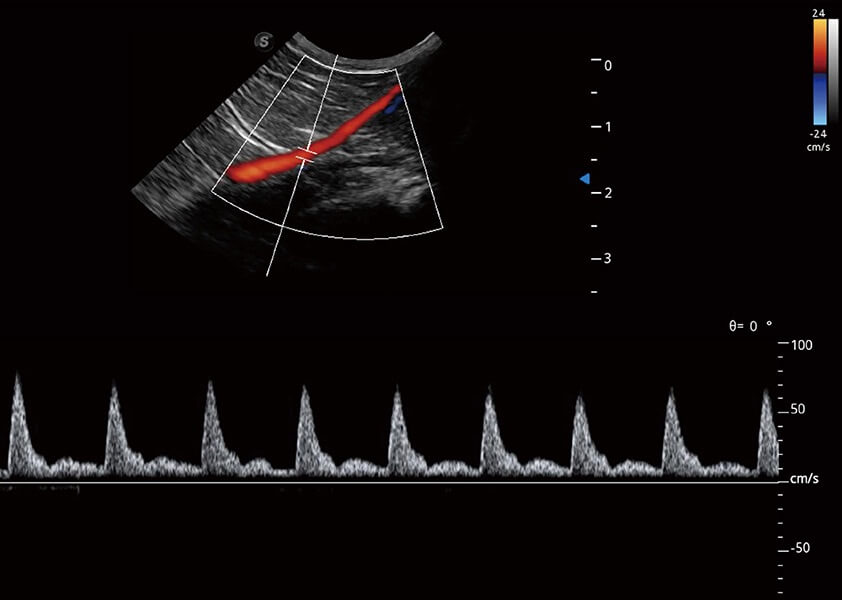

ProPet 60 作为一款高端台式动物超声设备,为动物医生的日常诊断提供了一系列贴合动物临床需求、解决临床实际问题的高级成像功能。凭借全系列高清探头,满足医生对腹部、心脏、生殖、浅表、肌骨等成像的所有需求,切实帮助您提升检查效率,提高诊断信心。

动物是人类最亲密的朋友和最值得信赖的伙伴。乐玩lewin国际也一直致力于探索动物专用的超声影像解决方案。 全新推出的ProPet系列,是乐玩lewin国际在动物超声影像智能化、专业化、精准化的一次跨越式革新。动物不能用言语来表述自己的不适,通过超声影像,ProPet系列搭建了动物医生与不同物种沟通的“桥梁”,为动物医生注入了“治愈之力”。